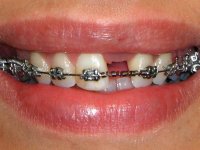

Tendo em conta a relação de Classe II molar e canina, o plano de tratamento contemplou a seguinte abordagem multidisciplinar:

1) Extracção do 2º pre-molar superior direito,

2) Tratamento ortodôntico com o objectivo de criar espaço entre as raízes e as coroas dos dentes 11 e 22,

3) Colocação de um implante no espaço criado na zona do 21 associada a uma regeneração óssea guiada da zona,

4) Reabilitar prostodonticamente o implante com um coto de oxido de zirconio e uma coroa de cerâmica vítrea prensada de dissilicato de lítio no sentido de obter o resultado estético pretendido.